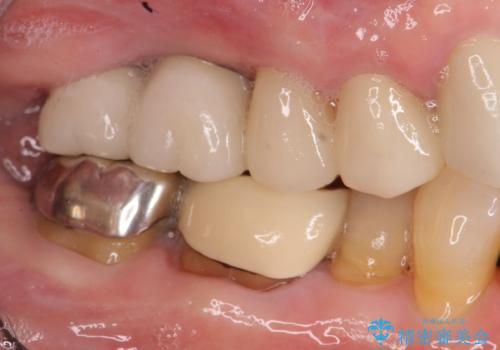

親知らず、ブリッジを抜去・撤去しインプラントを用いた咬合機能回復を行っていくこととしました。

- 123.2万円(インプラント×2・チタンカスタムアバットメント×2・ジルコニアクラウン×4・仮歯×4)費用は治療当時の料金となります

しっかりと噛めるようになったと同時に歯ブラシもしやすくなり、食生活がまた楽しめるようになったと喜んでいただくことができました。